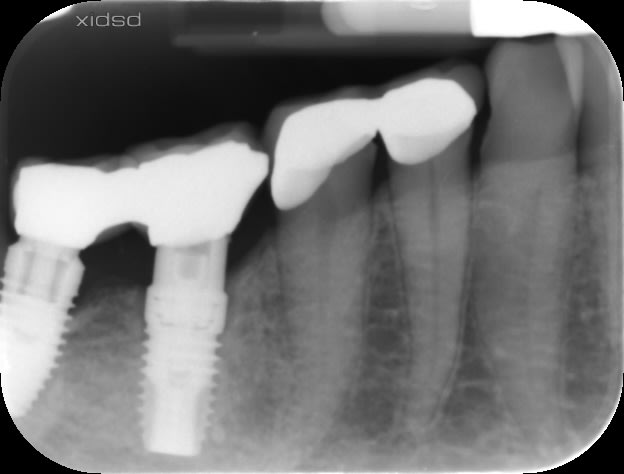

je cherche désespérément la marque de l'implant en 46.

Ce n'est pas un 3I, ni Eurotecchnika, ni Nobel, ni Victory.

en 46 implant violet avec pilier en trèfle a 6 feuilles

en 47, autre modèle, implant titane couleur acier, avec un pilier qui vient s'appuyer sur l'implant, mais intérieur de l'implant ressemble a un grand cône morse avec des pans. Je pense qu'un pilier provisoire a été utilisé

Celui en 46 est donc un Keystone prima connex mais en straight (droit)

la plateforme violette, c'est en général pour la plateforme 4.5mm

celui sur 47 vu la périimplantite => bassinet.... peu importe la marque, mais il a une bonne gueule de Nobel replace CC.....